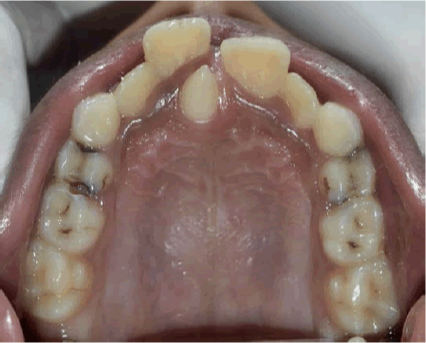

mesiodens

Supernumerary teeth (多生牙)